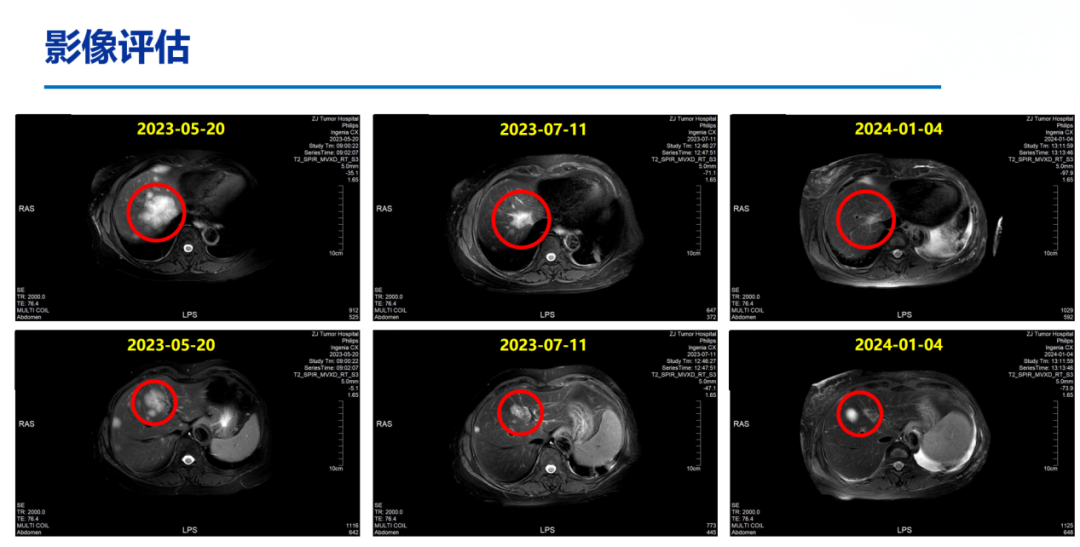

2023-05-24至2023-12-19予8周期“白蛋白紫杉醇125mg/m2 d1-8”化疗,最佳疗效为PR。

2024-01-05开始予氟维司群+达尔西利内分泌治疗维持。

2024-06-18上腹部MR:乳腺癌肝转移化疗后复查,对照2024.03.21MR:肝多发转移瘤,较前增多、增大。部分胸椎异常信号,考虑转移,较前相仿。

患者于2010年5月行左侧乳腺癌根治术,术后接受辅助化疗及他莫昔芬内分泌治疗,疾病稳定长达10年。2020年出现胸壁及淋巴结转移,后历经多线治疗,包括来曲唑治疗、化疗及CDK4/6抑制剂维持,疾病仍持续进展。基于DB-04研究的优异数据,患者于2024年7月启动二线T-DXd单药治疗,2周期后即达PR,显示出T-DXd在HR+/HER2低表达人群中的高效性。